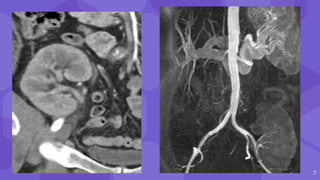

Renal artery stenosis

⬢ 10% of renal transplant patients

⬢ first post transplant week

⬢ also several years after

⬢ M/C in cadaveric transplants, transplants with

multiple renal arteries, and patients with

complex vascular anastomosis